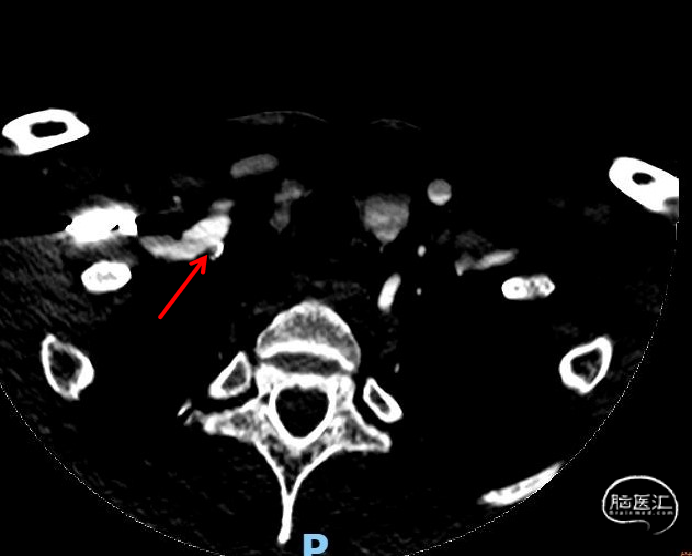

术前头颈部CTA示:(1)左侧锁骨下动脉、左颈总动脉、右锁骨下动脉起始部、双侧颈内动脉粥样硬化表现。(2)右侧椎动脉起始部粥样硬化表现,管腔中-重度狭窄。

术前脑血管造影示:右侧椎动脉V1段重度狭窄。